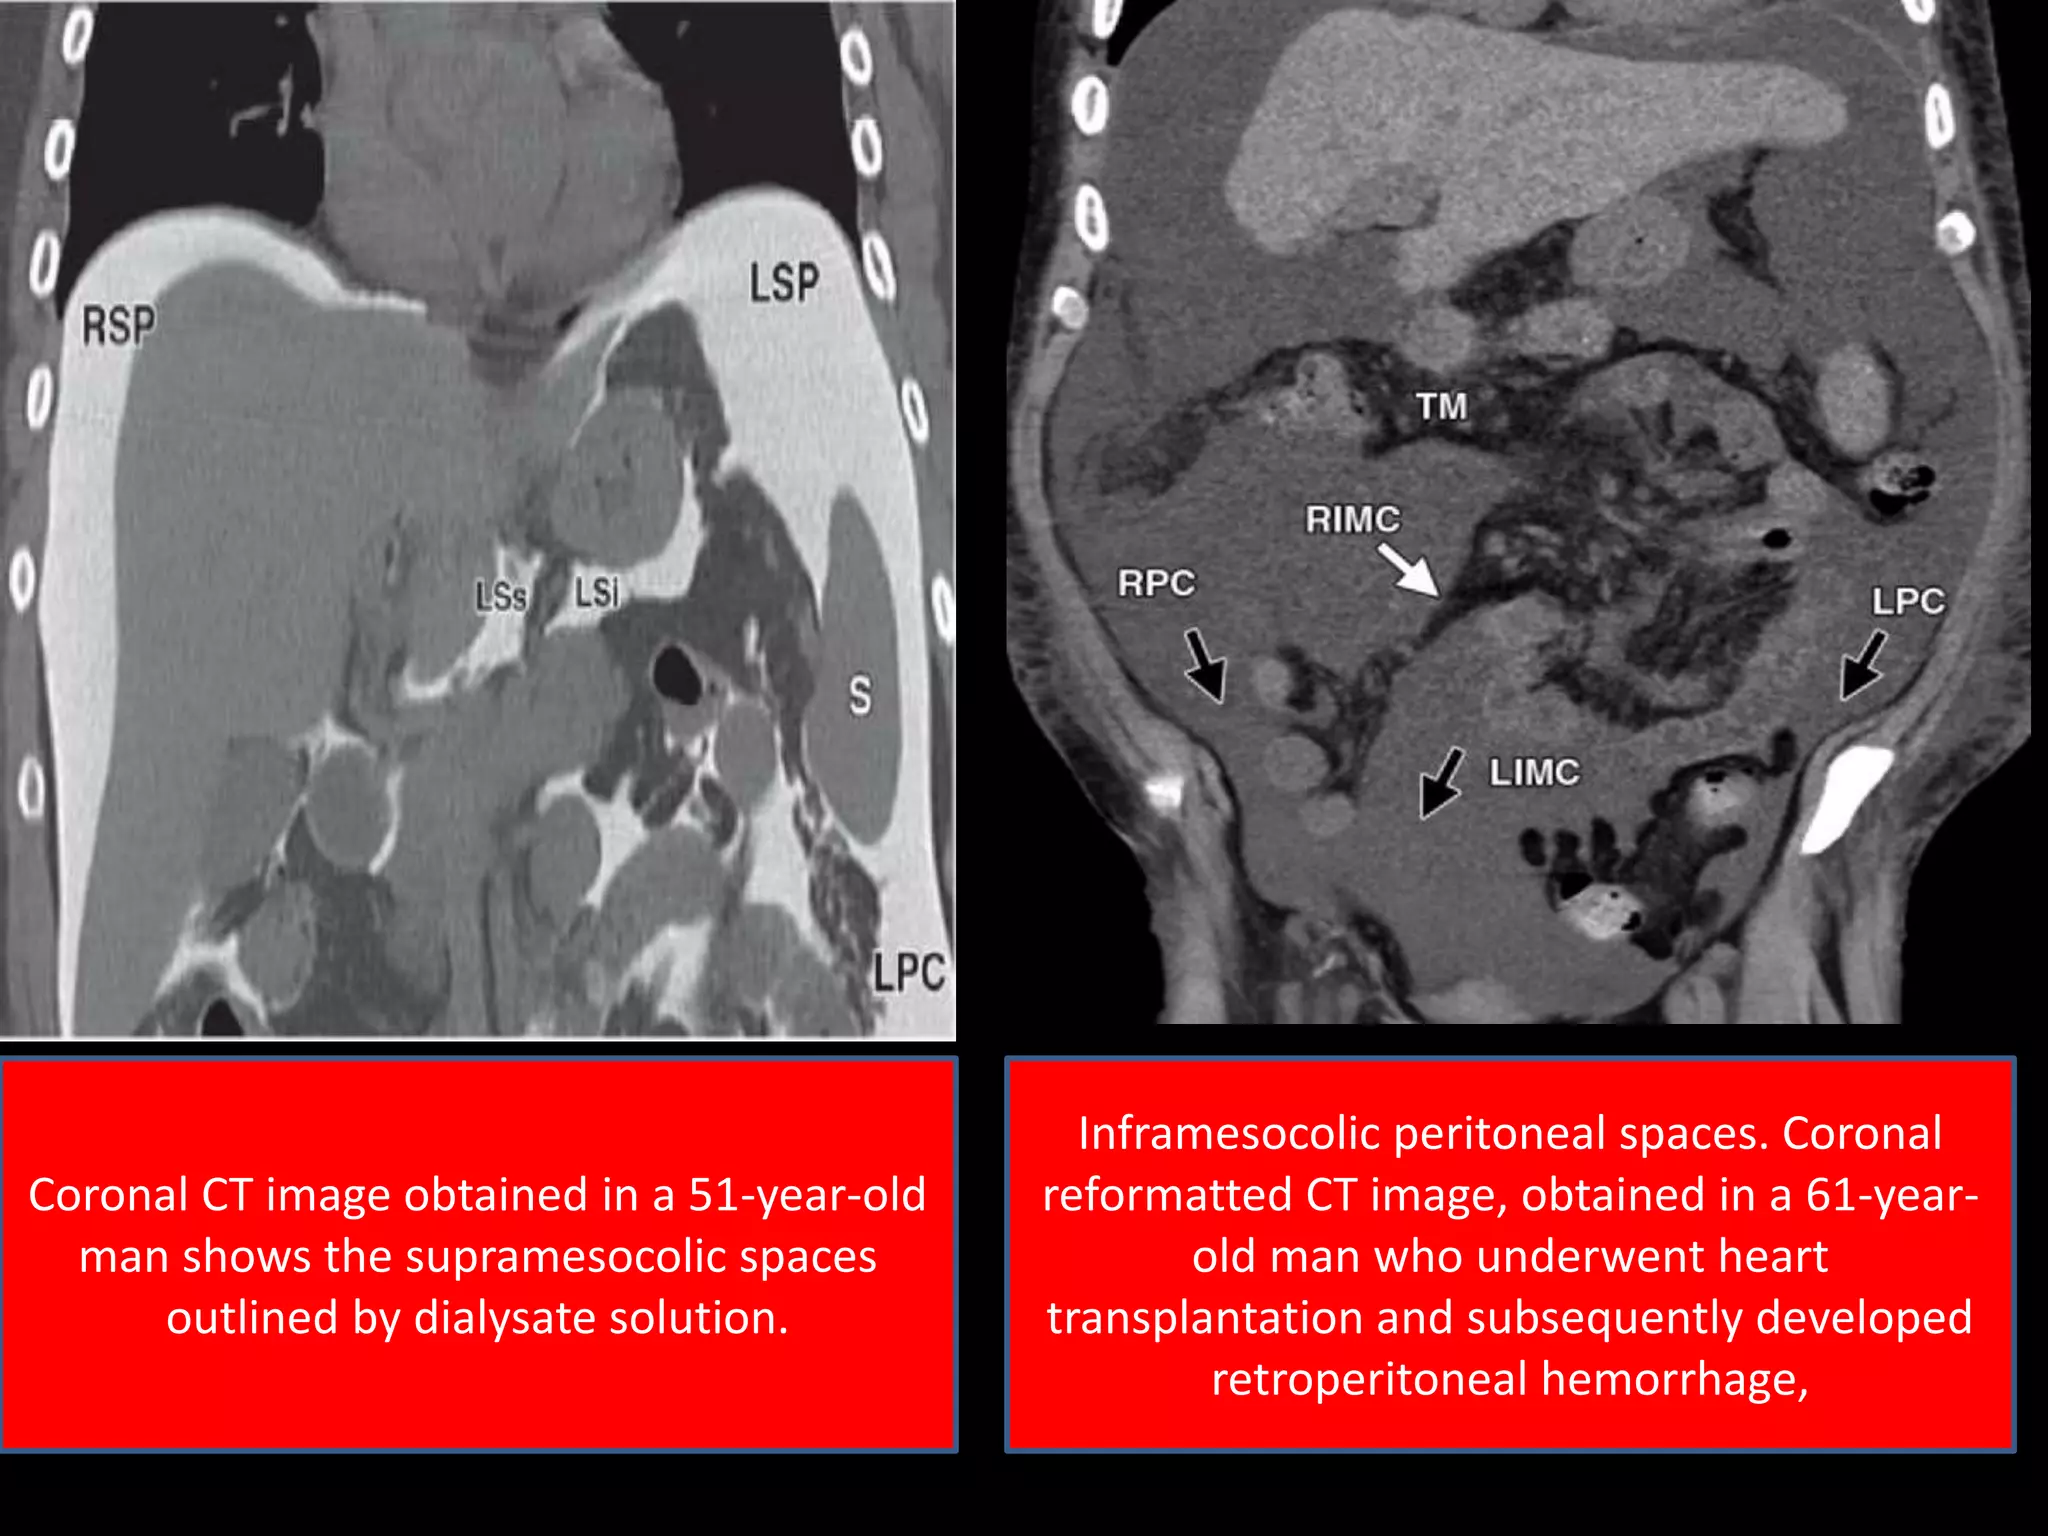

Coronal CT image obtained in a 51-year-old

man shows the supramesocolic spaces

outlined by dialysate solution.

Inframesocolic peritoneal spaces. Coronal

reformatted CT image, obtained in a 61-year-

old man who underwent heart

transplantation and subsequently developed

retroperitoneal hemorrhage,